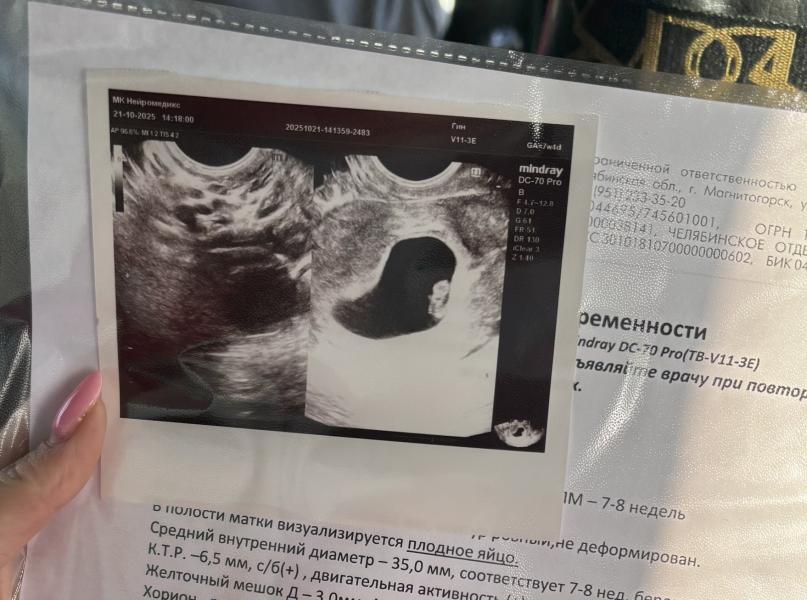

21.10 ездила на узи , 6 Нед 4 дня.

Все хорошо, эмбриончик наш видно, слава богу.

Сердечко уже бьется🙏🏻🙈